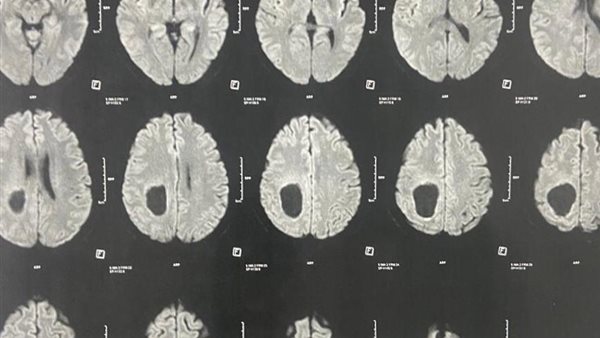

ومن جانبه، أوضح الدكتور مجدي القاضي، عميد كلية الطب البشري ورئيس مجلس إدارة المستشفيات الجامعية، أن المريض كان يعاني من اضطراب بدرجة الوعي وشلل نصفي بالجانب الأيسر، وتبين من الفحوصات وجود ورم بالمخ بحجم ٧×٥×٤ سم، وقد تم استئصاله بالكامل خلال جراحة استغرقت ٤ ساعات، مشيرًا إلى أن الفريق الجراحي استخدم تقنية حديثة تعتمد على حقن الصبغات الورمية لتحديد حدود الورم بدقة.

وأشار الدكتور أحمد كمال عبدالحميد، المدير التنفيذي للمستشفيات الجامعية واستاذ جراحة المخ والأعصاب والعمود الفقري، والذي أجرى الجراحة، إلى أن العملية تمت باستخدام ميكروسكوب جراحي متطور، والحفار الكهربائي لفتح عظام الجمجمة، مما ساهم في الوصول الآمن إلى الورم واستئصاله بالكامل دون التأثير على الأنسجة الحيوية. مضيفًا أن المريض استعاد وعيه بالكامل بعد الجراحة، وعادت حركة الأطراف إلى طبيعتها.